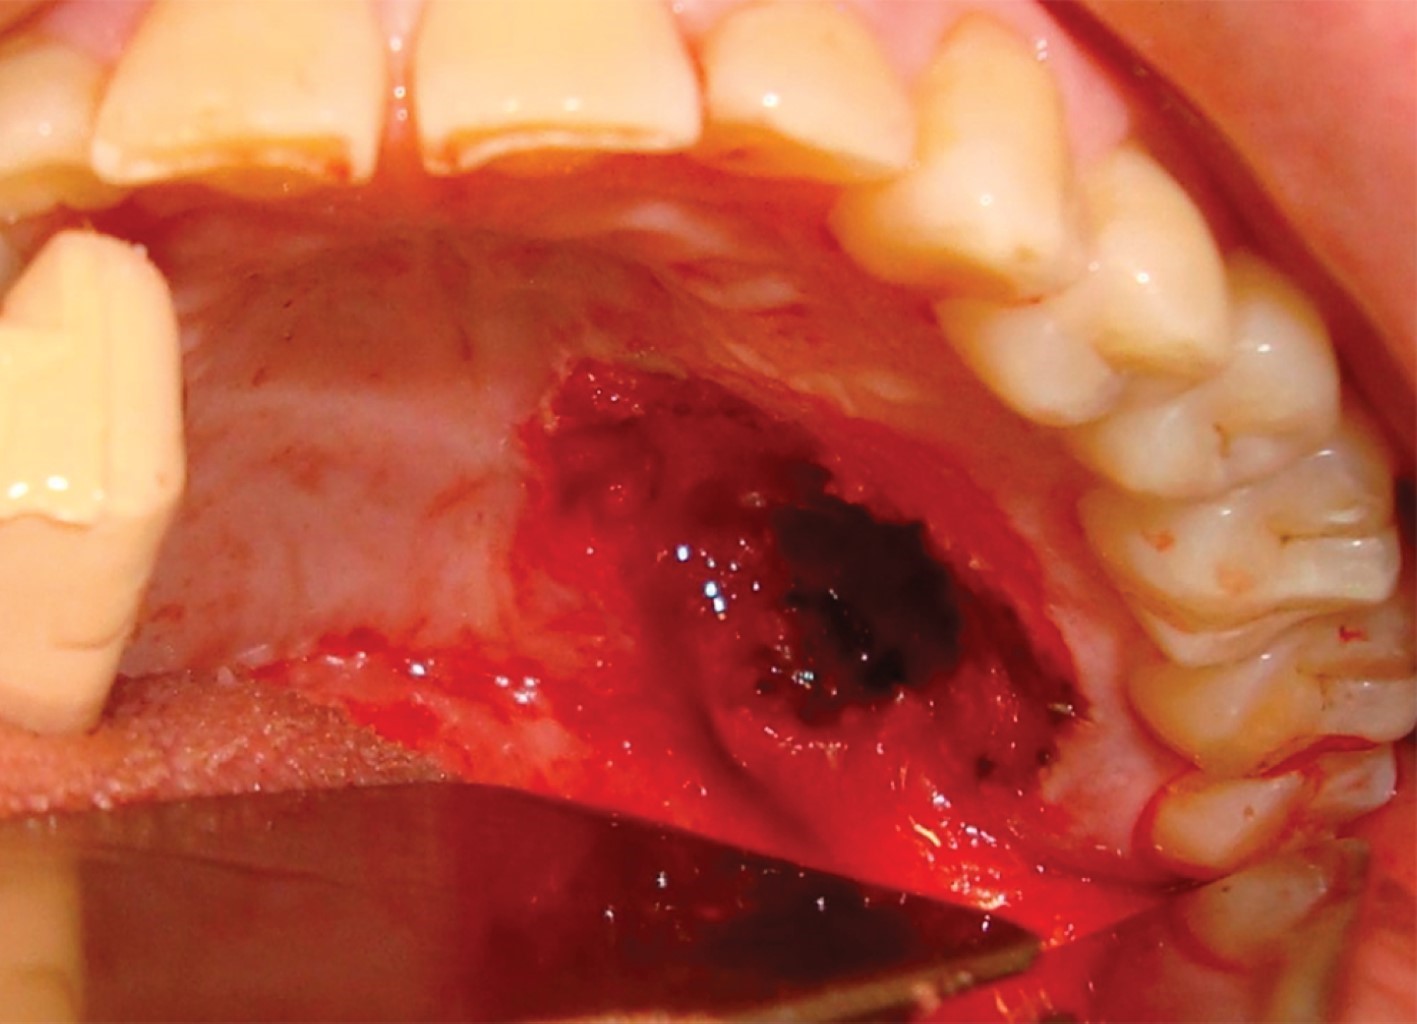

El paciente es remitido con informe de biopsia incisional, la cual detalla mucosa revestida por epitelio escamoso con ligera acantosis y foco de exocitosis linfocitaria. Corion con infiltrado inflamatorio linfoplasmocitario y presencia de proliferación fusocelular entremezclada con fibrosis que comprime estructuras vasculares (Figura 2). Se realizaron técnicas de inmunomarcación con vimentina, actina, demina y CD31, resultó la proliferación descrita positiva con vimentina y actina, en tanto que negativa para desmina y CD31; posteriormente, se arribó al diagnóstico de miofibroma. Bajo anestesia general balanceada se realizó la enucleación marginal de la lesión (Figuras 3 y 4). El análisis histopatológico de la pieza quirúrgica confirma el diagnóstico prequirúrgico. No se evidenciaron signos de recurrencia de la enfermedad luego de 24 meses de controles (Figura 5).

Figura 2

Figura 3

Figura 4